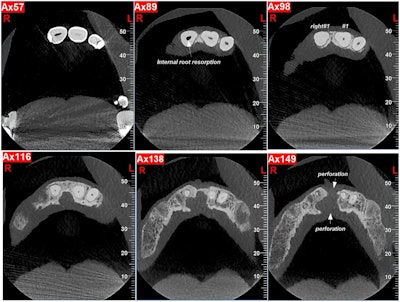

Fig. 1: Initial images.Images and captions courtesy of Heydarzadeh et al. Licensed under CC BY 4.0.

Figure 2: Occlusal views of CBCT images showing internal root resorption, bone loss, and perforation of the cortical plates.